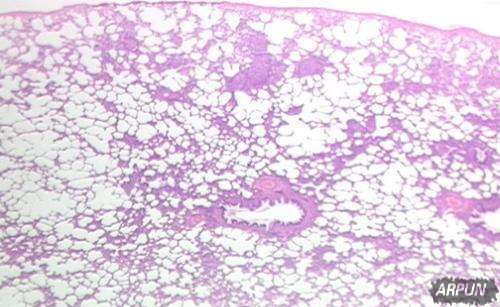

这里是它看起来的样子: